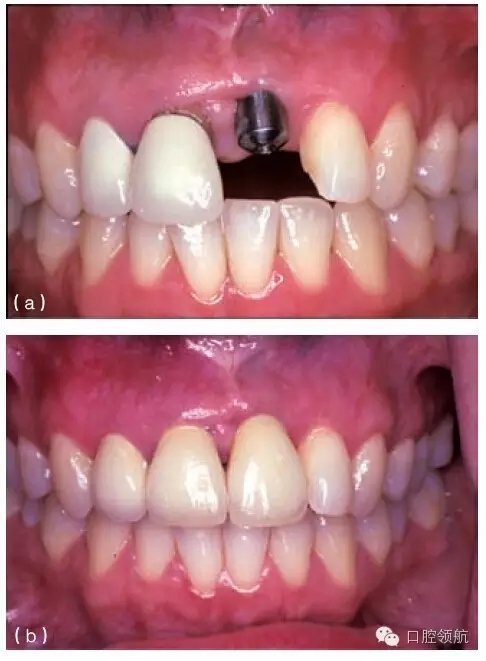

其他的美學問題與種植體植入位置不當(圖10.20a,b),以及植入前存在骨吸收有關。骨吸收的存在使種植體無法植入到理想位置,造成單冠之間或是固定局部義齒的橋體之間存在頸部間隙(圖10.21)。

圖10.20 (a)中切牙種植體的位置太偏唇側,采用定制的基臺盡可能補償頰側的錯位。(b)一并更換相鄰的兩個冠修復體以獲得更滿意的結果。

種植體植入太偏唇側,將造成明顯的美學問題,而且通常很難克服(圖10.20a,b)。